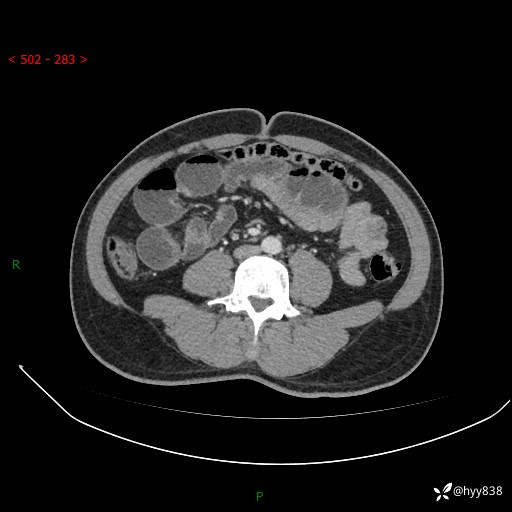

年轻男性,腹痛5月余。除了肠梗阻,你还能看到什么---结果公布~

主诉:腹痛5月余。

现病史:患者于5月前无明显诱因开始出现腹痛,上明显,为间断性胀痛不适,无畏寒发热,无心慌气促等特殊不适,遂来我院。我院门诊遂以“腹痛原因待查”收入我科。 起病以来,患者精神、饮食、睡眠欠佳,大小便正常。体力体重无明显变化。

腹部CT增强扫描(动脉期+静脉期)